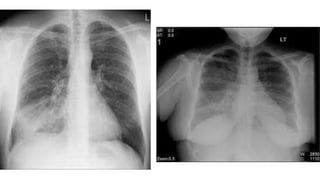

• Chest xray

• new radiological infiltrates(In xray or CT scan)

• #16 Cough (with or without sputum production), dyspnea, and pleuritic chest pain are among the most common symptoms associated with CAP. Signs of pneumonia on physical examination include tachypnea, increased work of breathing, and adventitious breath sounds, including rales/crackles and rhonchi. Tactile fremitus, egophony, and dullness to percussion also suggest pneumonia. These signs and symptoms result from the accumulation of white blood cells (WBCs), fluid, and proteins in the alveolar space. Hypoxemia can result from the subsequent impairment of alveolar gas exchange. On chest radiograph, accumulation of WBCs and fluid within the alveoli appears as pulmonary opacities